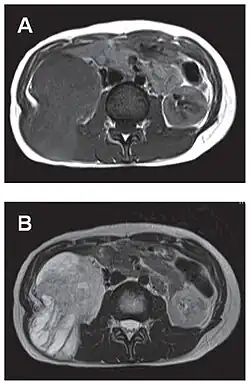

- Tumeur fibreuse solitaire du rétropéritoine

Aspect tomodensitométrique, sans (A) puis avec (B) injection de produit de contraste[44].

Aspect IRM, en séquence T1 (A) et T2 (B)[44].

L'imagerie par résonance magnétique permet une exploration complémentaire dans certaines localisations. Elle est surtout réalisée pour les tumeurs du système nerveux central[8],[12],[43], du foie et du pelvis[31],[41]. Elle évalue mieux les différences de densité intra-tumorale et permet d'affirmer l'absence d'envahissement des tissus mous et des structures osseuses voisines[20]. Les tumeurs fibreuses solitaires ont un aspect d'isosignal en séquence T1 et d'hypersignal en T2, et se rehaussent après l'injection de gadolinium[31]. Cependant, dans le système nerveux central, elles ne présentent pas de critères caractéristiques permettant de poser un diagnostic de manière uniquement radiologique[12] et, en pré-opératoire, sont souvent confondues avec un méningiome[43].